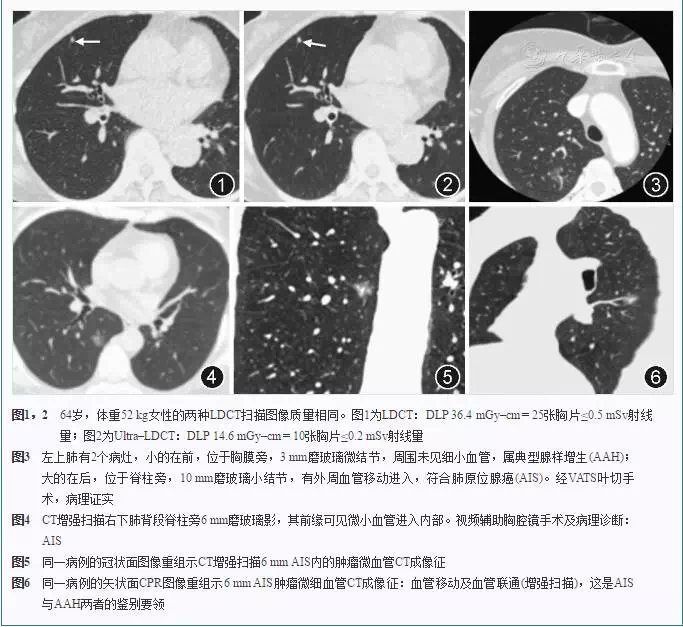

随着影像技术的高速发展,肺结节的检出率逐年增高,大部分结节属于良性结节,需要每年随访,少部分结节属于高危结节,需要定期3-6个月进行复查,而极少部分超高危结节临床医生会考虑直接进行手术切除,将其扼杀在摇篮里。由此可见,CT筛查肺部结节的重要性。在CT检查中,辐射危害成为人们最为担心之事,我院新购置的飞利浦显微CT在获得高质量图像的同时,较常规CT可有效降低60%-80%辐射剂量————即一次胸部CT的辐射剂量仅相当于10次胸片,让CT检查更加安全。

我院的超高端CT还具有扫描速度快,图像分辨率高的特点,胸部及腹部只需3秒即可完成扫描,其独特的IMR显微平台,对微小病灶的检出方面具有独特优势,是目前体检、复查的最佳选择!